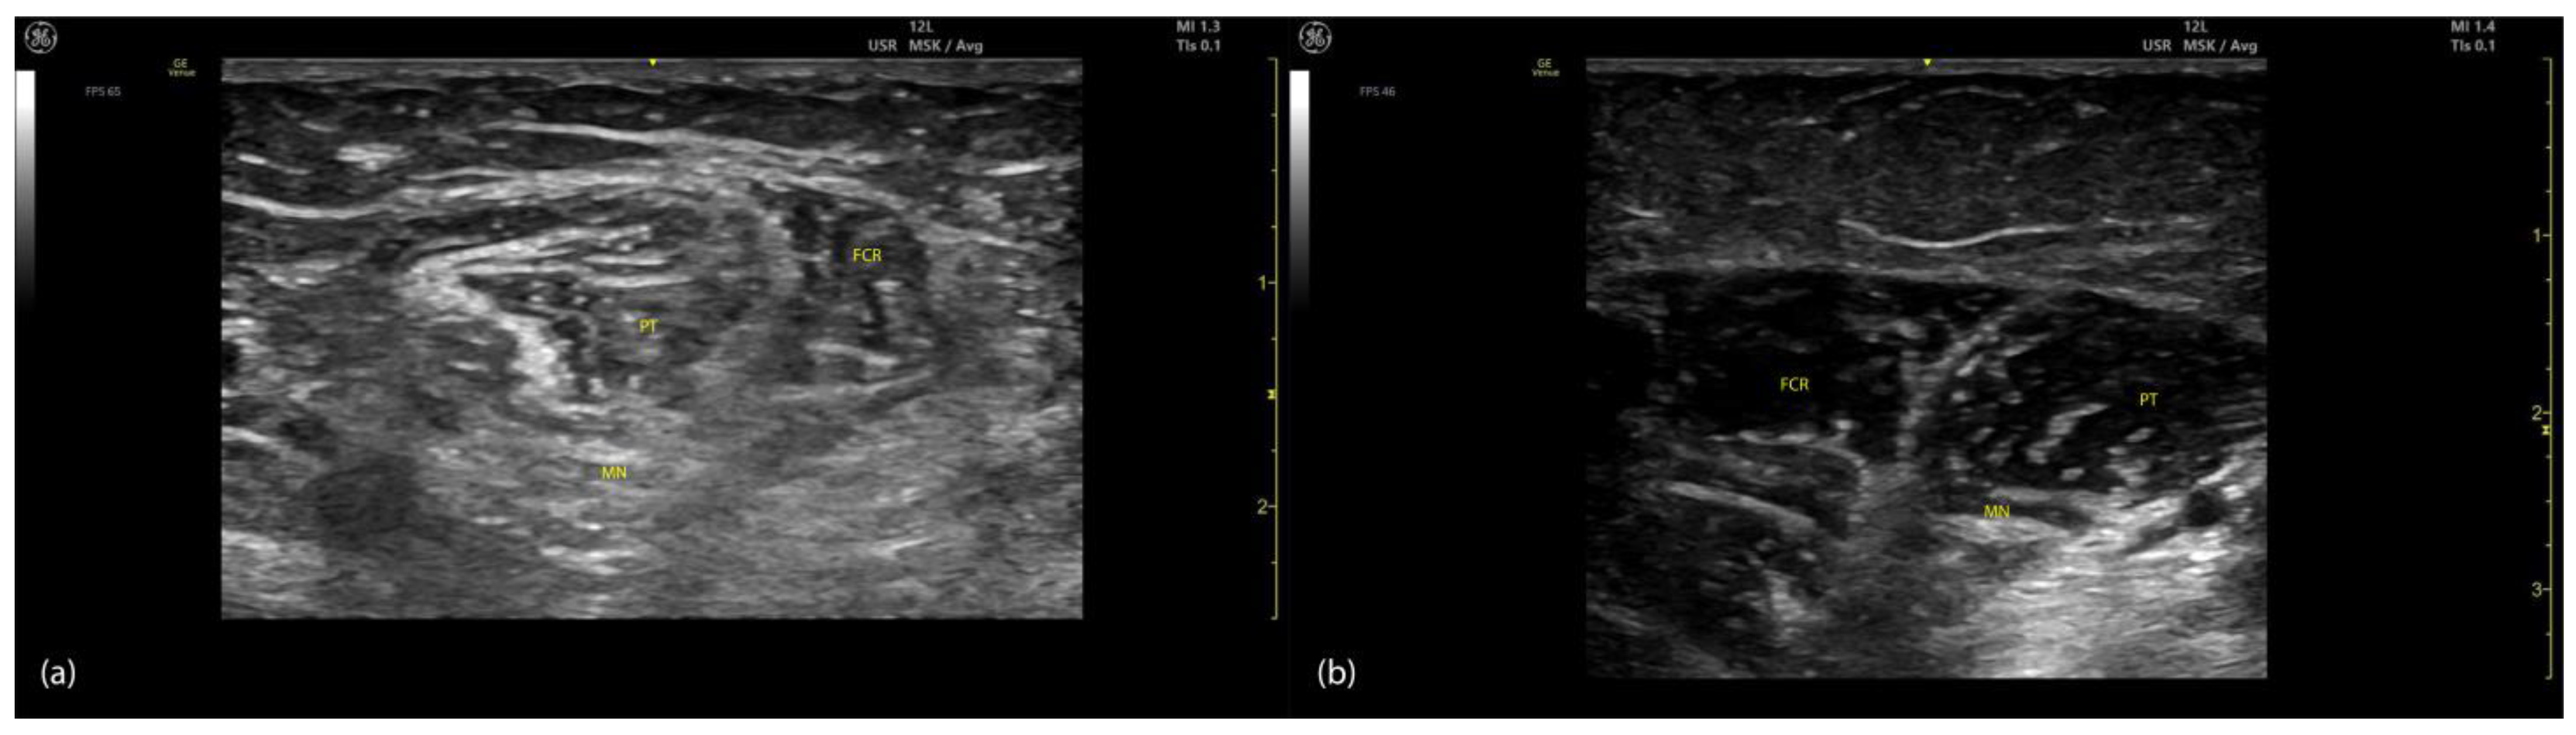

2.1.2. Ultrasound Identification

- The PT, which appears oval-shaped on the lateral side;

- The flexor carpi radialis (FCR), which appears triangular-shaped on the medial side [8].

2.1.3. Key Ultrasound Landmarks (Figure 1)

- Muscle position: The PT is the first muscle mass from radial to ulnar on the volar aspect of the forearm [9].

- Intramuscular tendon: In the lateral portion of the muscle, it is positioned longitudinally along the muscle at this level.

- Internal fascia: The fascia separates the humeral (PTHH) and ulnar heads (PTUH) of the PT, while the external fascia distinctly demarcates the PT from adjacent muscle masses, facilitating precise BoNT-A injection.

- Median nerve: The nerve is located deep to the PT, approximately 2 cm distal to the elbow crease. Dynamic evaluation cranially towards the arm reveals the nerve transitioning to the lateral aspect of the muscle alongside the brachial artery [10].

- Dynamic evaluation (Video S1): Scanning proximally toward the medial epicondyle shows an increase in the PT muscle belly size and a concurrent decrease in the size of the FCR. At this level, the intramuscular fascia specific to the PT becomes evident, separating the two muscle heads—the humeral head and the ulnar head—allowing for individual targeting [11].